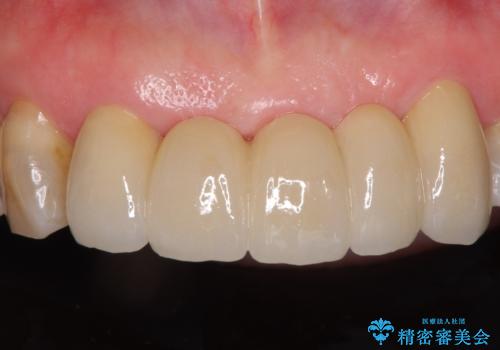

装着されていたブリッジは、支台となっている歯と欠損している歯で色が大きく異なっていましたが、オールセラミックとしたことで、全体的に色調の整った仕上がりとなりました。

歯肉ラインがきれいに整い、患者様には大変満足していただきました。